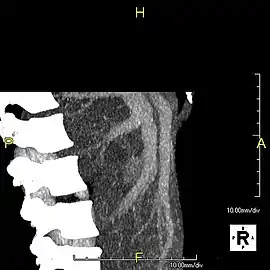

CT scan showing an adult liver in the axial plane

Organogenesis, the development of the organs, takes place from the third to the eighth week during embryogenesis. The origins of the liver lie in both the ventral portion of the foregut endoderm (endoderm being one of the three embryonic germ layers) and the constituents of the adjacent septum transversum mesenchyme. In the human embryo, the hepatic diverticulum is the tube of endoderm that extends out from the foregut into the surrounding mesenchyme. The mesenchyme of septum transversum induces this endoderm to proliferate, to branch, and to form the glandular epithelium of the liver. A portion of the hepatic diverticulum (that region closest to the digestive tube) continues to function as the drainage duct of the liver, and a branch from this duct produces the gallbladder.[35] Besides signals from the septum transversum mesenchyme, fibroblast growth factor from the developing heart also contributes to hepatic competence, along with retinoic acid emanating from the lateral plate mesoderm. The hepatic endodermal cells undergo a morphological transition from columnar to pseudostratified resulting in thickening into the early liver bud. Their expansion forms a population of the bipotential hepatoblasts.[36] Hepatic stellate cells are derived from mesenchyme.[37]